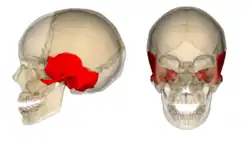

A caixa craniana é formada pelos seguintes ossos:

Osso parietal (par)

Osso parietal (par)